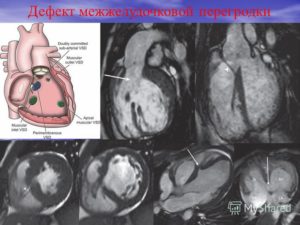

Дефект межжелудочковой перегородки